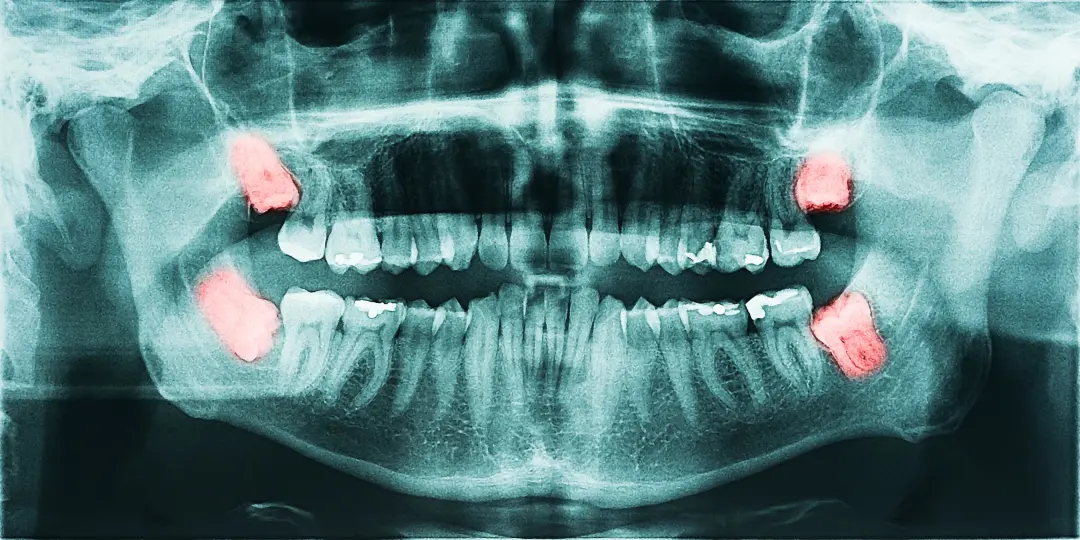

(一(yī)) 阻生(shēng)齒

由于生(shēng)長(cháng)空(kōng)間(j≠↔σiān)的(de)不(bù)足,導緻智齒不(bù)能(néng)正常萌✘≈出,部分(fēn)或者全部埋伏在牙龈牙槽骨裡(lǐ)Ωε÷ε面,或是(shì)側卧、倒立、斜靠等。總之就(jiù"↕≤)是(shì)長(cháng)歪了(le)的(de)智齒。

像這(zhè)種阻生(shēng)牙齒,不(bù)僅清潔難度大(dà),容易滋生(sh>≥αēng)細菌,發生(shēng)齲壞。嚴重的(de)還(hái)可(≤★↓kě)能(néng)引起智齒冠周炎,導緻咀嚼、吞咽疼痛加劇(jù)。

(二)侵犯鄰牙&n®>≥bsp;

歪倒著(zhe)長(cháng)的(de)智齒₹₩,極易将鄰牙頂壞,造成鄰牙牙根被吸收、牙冠損壞等。

此外(wài),二者之間(jiān)形成的(de)夾角也(yě≤Ω)容易藏污納垢,引起鄰牙的(de)齲壞。